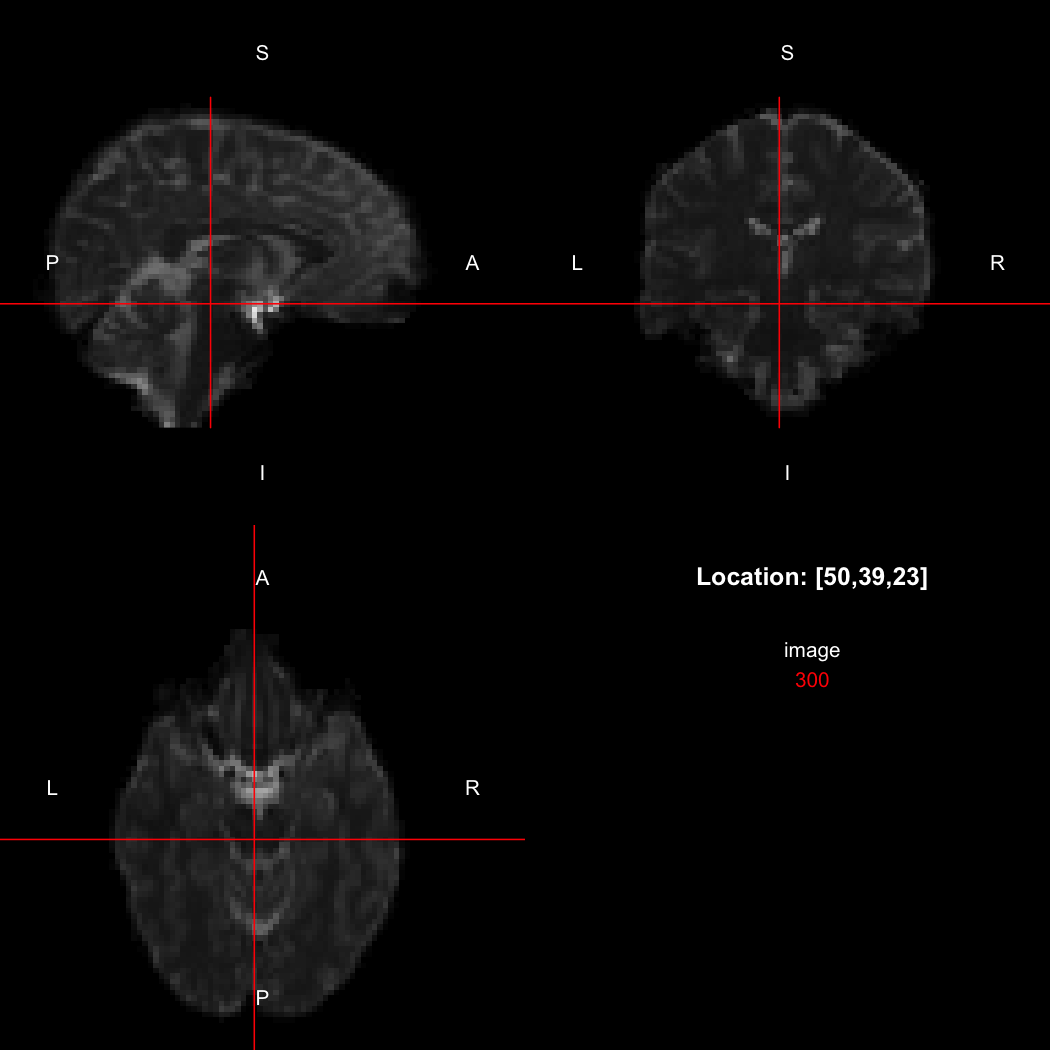

image <- readNifti(system.file("extdata", "example.nii.gz", package="RNifti"))We can also use the RNifti image viewer to visualise the

image.

view(image)